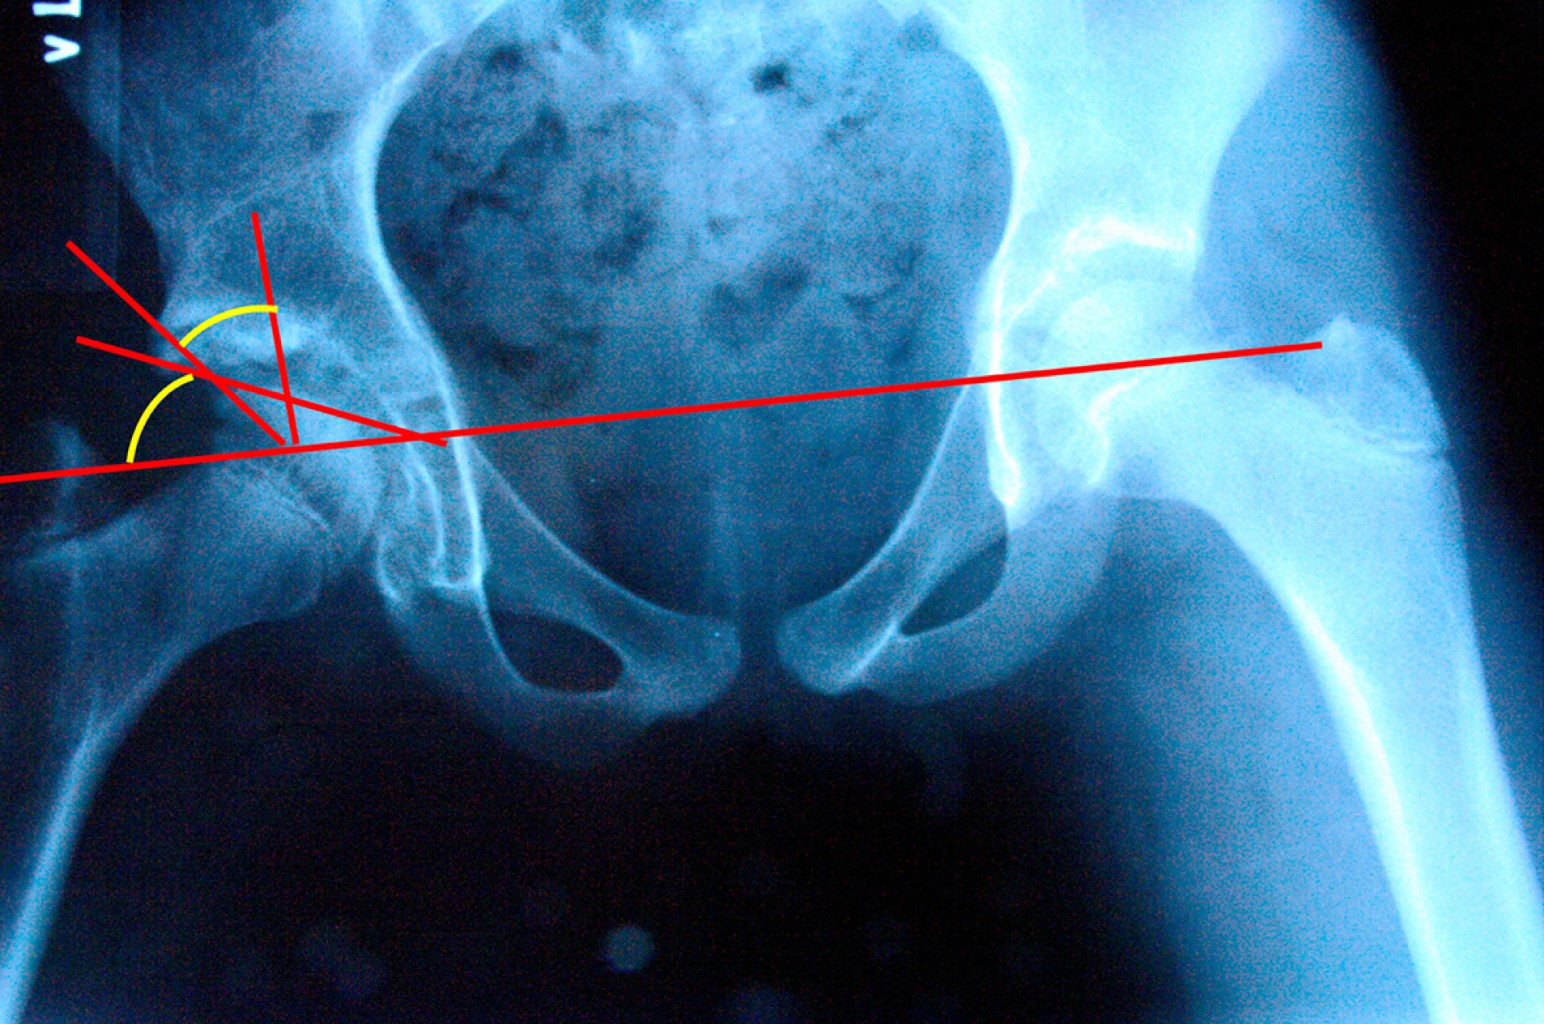

En todos los casos con DDC estudiados se les realizó miotomía de aductores con tenotomía del psoas por medio de abordaje medial transversal a nivel de la ingle; para la reducción de la cadera, se abordó por vía anterolateral y se realizó un abordaje tipo Smith-Peterson, se desinsertan el sartorio y el recto anterior, hasta visualizar lo más posible la cápsula articular y apreciar la parte más medial de la cápsula de la cadera; posteriormente, se realiza una fractura de la epífisis Salter tipo 1 a nivel de la cresta iliaca y se desperiostiza la cara interna y externa del iliaco hasta la escotadura ciática mayor. A continuación, se realiza una capsulotomía en "T" con liberación medial de la cápsula articular con resección del ligamento redondo, resección del ligamento transverso y pulvinal, evitando lesionar el cartílago articular del acetábulo y sin resección del labrum. Se reduce la cadera y se fija con un clavo Kirschner, dejándolo en el tercio medio o inferior del cuello femoral (Figura 1). Después, mediante un abordaje lateral a nivel femoral se realiza osteotomía varizante y desrotadora, esto último cuando hay más de 60o de anteversión, preservando de 15-20o de anteversión femoral y una diafisectomía de 8-10 mm como máximo para evitar una subluxación por tener cadera inestable; la osteotomía femoral se fija con una placa DCP de 3.5 mm con dos tornillos proximales y dos distales. Posteriormente se realiza osteotomía tipo Salter para mejorar la cobertura acetabular dirigiendo el extremo distal hacia la parte lateral y anterior para mejorar el índice acetabular y la cobertura lateral, colocando un injerto en "V" a nivel de la apertura de la osteotomía de Salter, fijando ésta con dos clavos de Kirschner, estas agujas no deben atravesar la superficie articular del acetábulo. Durante todos los procedimientos se toman imágenes de control con intensificador de imagen para valorar la reducción de la cadera, la osteotomía femoral y la osteotomía de Salter (Figura 2). En todas las caderas se realizó capsulorrafia en "V"; se reinsertan los músculos sartorios y el recto anterior en su porción directa y refleja, y se sutura la epífisis de la cresta iliaca con sus inserciones musculares respectivas. Finalmente, se coloca un aparato de yeso tipo Callot a 20o de flexión de cadera; 20o de abducción y ligera rotación interna, con flexión de rodillas, el cual se mantiene por seis semanas, tiempo en el que también se retira el clavo Kirschner y posteriormente se coloca aparato de yeso tipo Bachelor por seis semanas más.

Figura 1